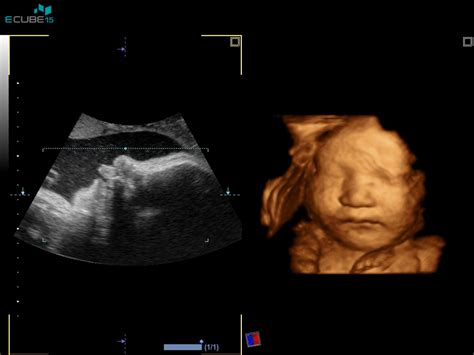

- 3D/4D ultrazvok ploda v prvem trimesečju ob potrditvi nosečnosti ali nuhani svetlini: Omogoča bolj realističen prikaz ploda. Cena je 25 €.

- Morfologija ploda (specialistična preiskava razvoja ploda) in 3D/4D ultrazvočni pregled ploda: Kombinacija podrobnega pregleda in 3D/4D prikaza. Cena je 110 €.

- 3D/4D ultrazvok ploda z vključeno kontrolo plodove rasti, lege in teže: Kombinacija vizualnega prikaza in spremljanja rasti. Cena je 80 €.

- 3D/4D ultrazvok ploda z vključeno kontrolo plodove rasti, lege in teže ter Dopplersko ultrazvočno preiskavo pretokov skozi popkovnične žile za oceno stanja ploda: Najobsežnejši ultrazvočni pregled. Cena je 100 €.